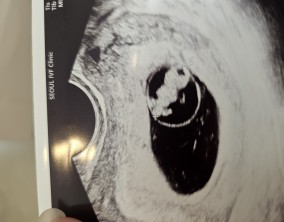

서울IVF와 한 팀이 된 순간, 길이 열렸습니다

1) 전문성과 체계적인 치료 이유정 원장님께서 치료 단계마다 꼼꼼하게 설명해주셔서, 내가 어떤 과정에 있는지 명확하게 이해할 수 있었습니다. 불안함을 줄여주는 체계적인 시스…

이유정 원장님이라면 해낼 수 있다

이유정 원장님은 친언니처럼 솔직하고, 환자의 상황을 정확히 판단하는 냉철함에 따뜻함까지 가진 분이셨어요. 데스크·상담·채혈·시술실 모든 선생님들까지 정말 다정하고 따뜻…